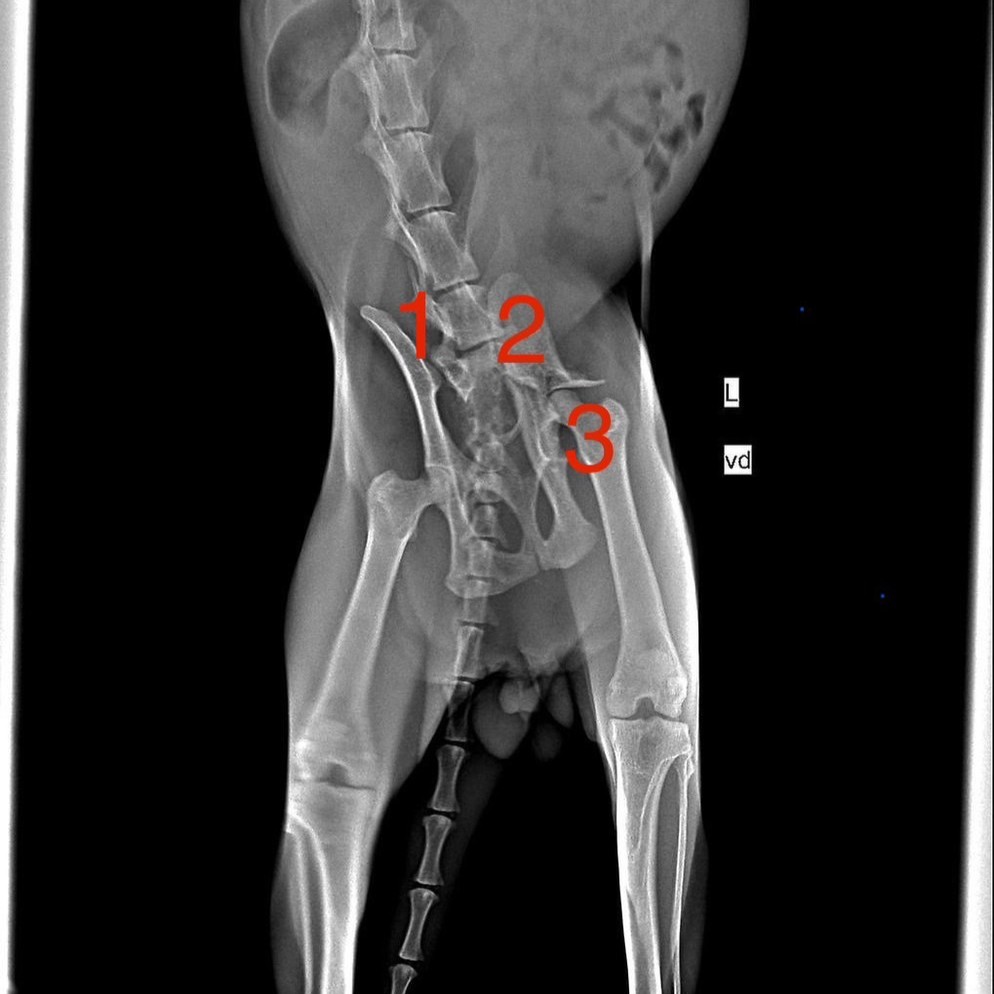

อาการ/โรค: สะโพกหัก (รักษาเสร็จรับกลับ)